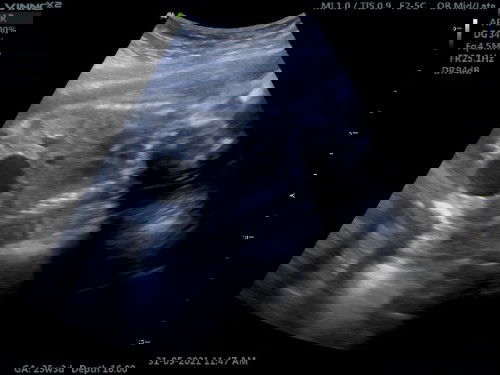

Saya bru buat detail scan kt kandungan... Tp... Dokter kata pundi kencing bayi sy besar kena rujuk pakar... Apa punca ya pundi kencing bayi saya jadi besar? Ada pengalaman x? Sy dh 26minggu...#ingintahu